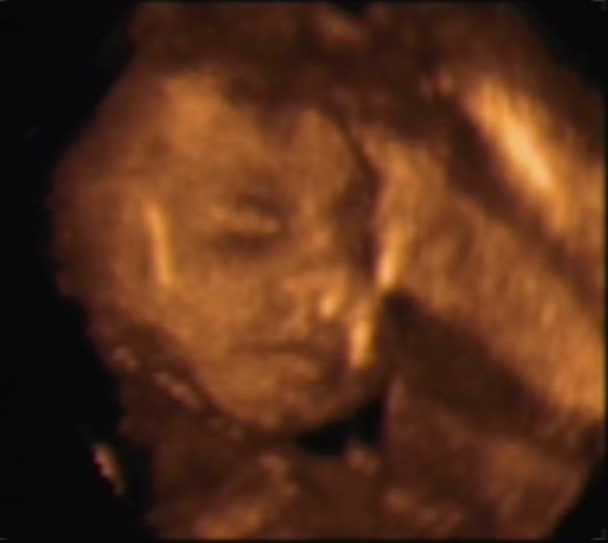

19.05.2018 - 25недель и 1 день. Были на 3Д УЗИ. Дэнчик чувствует себя хорошо) вес 790 грамм, рост 32,7 см. Доктор сказала - красавчик))